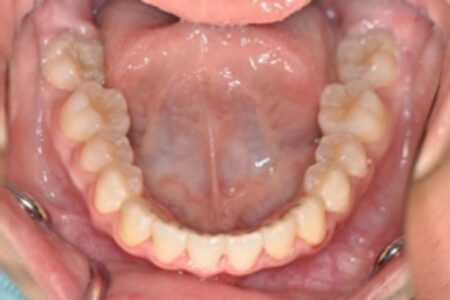

| 治療内容の詳細 | 初診時10歳の女性で、全体的ながたつきを主訴として来院されました。 検査の結果、交叉咬合を伴う、アングルⅠ級不正咬合と診断しました。 治療としては、反対咬合を改善するための装置で上顎前歯部を前方にだすと同時に上あごを広げ、セルフライゲーションブラケット装置(デーモンシステム)で歯の配列を行いました。 治療期間は2年11か月でした。 |